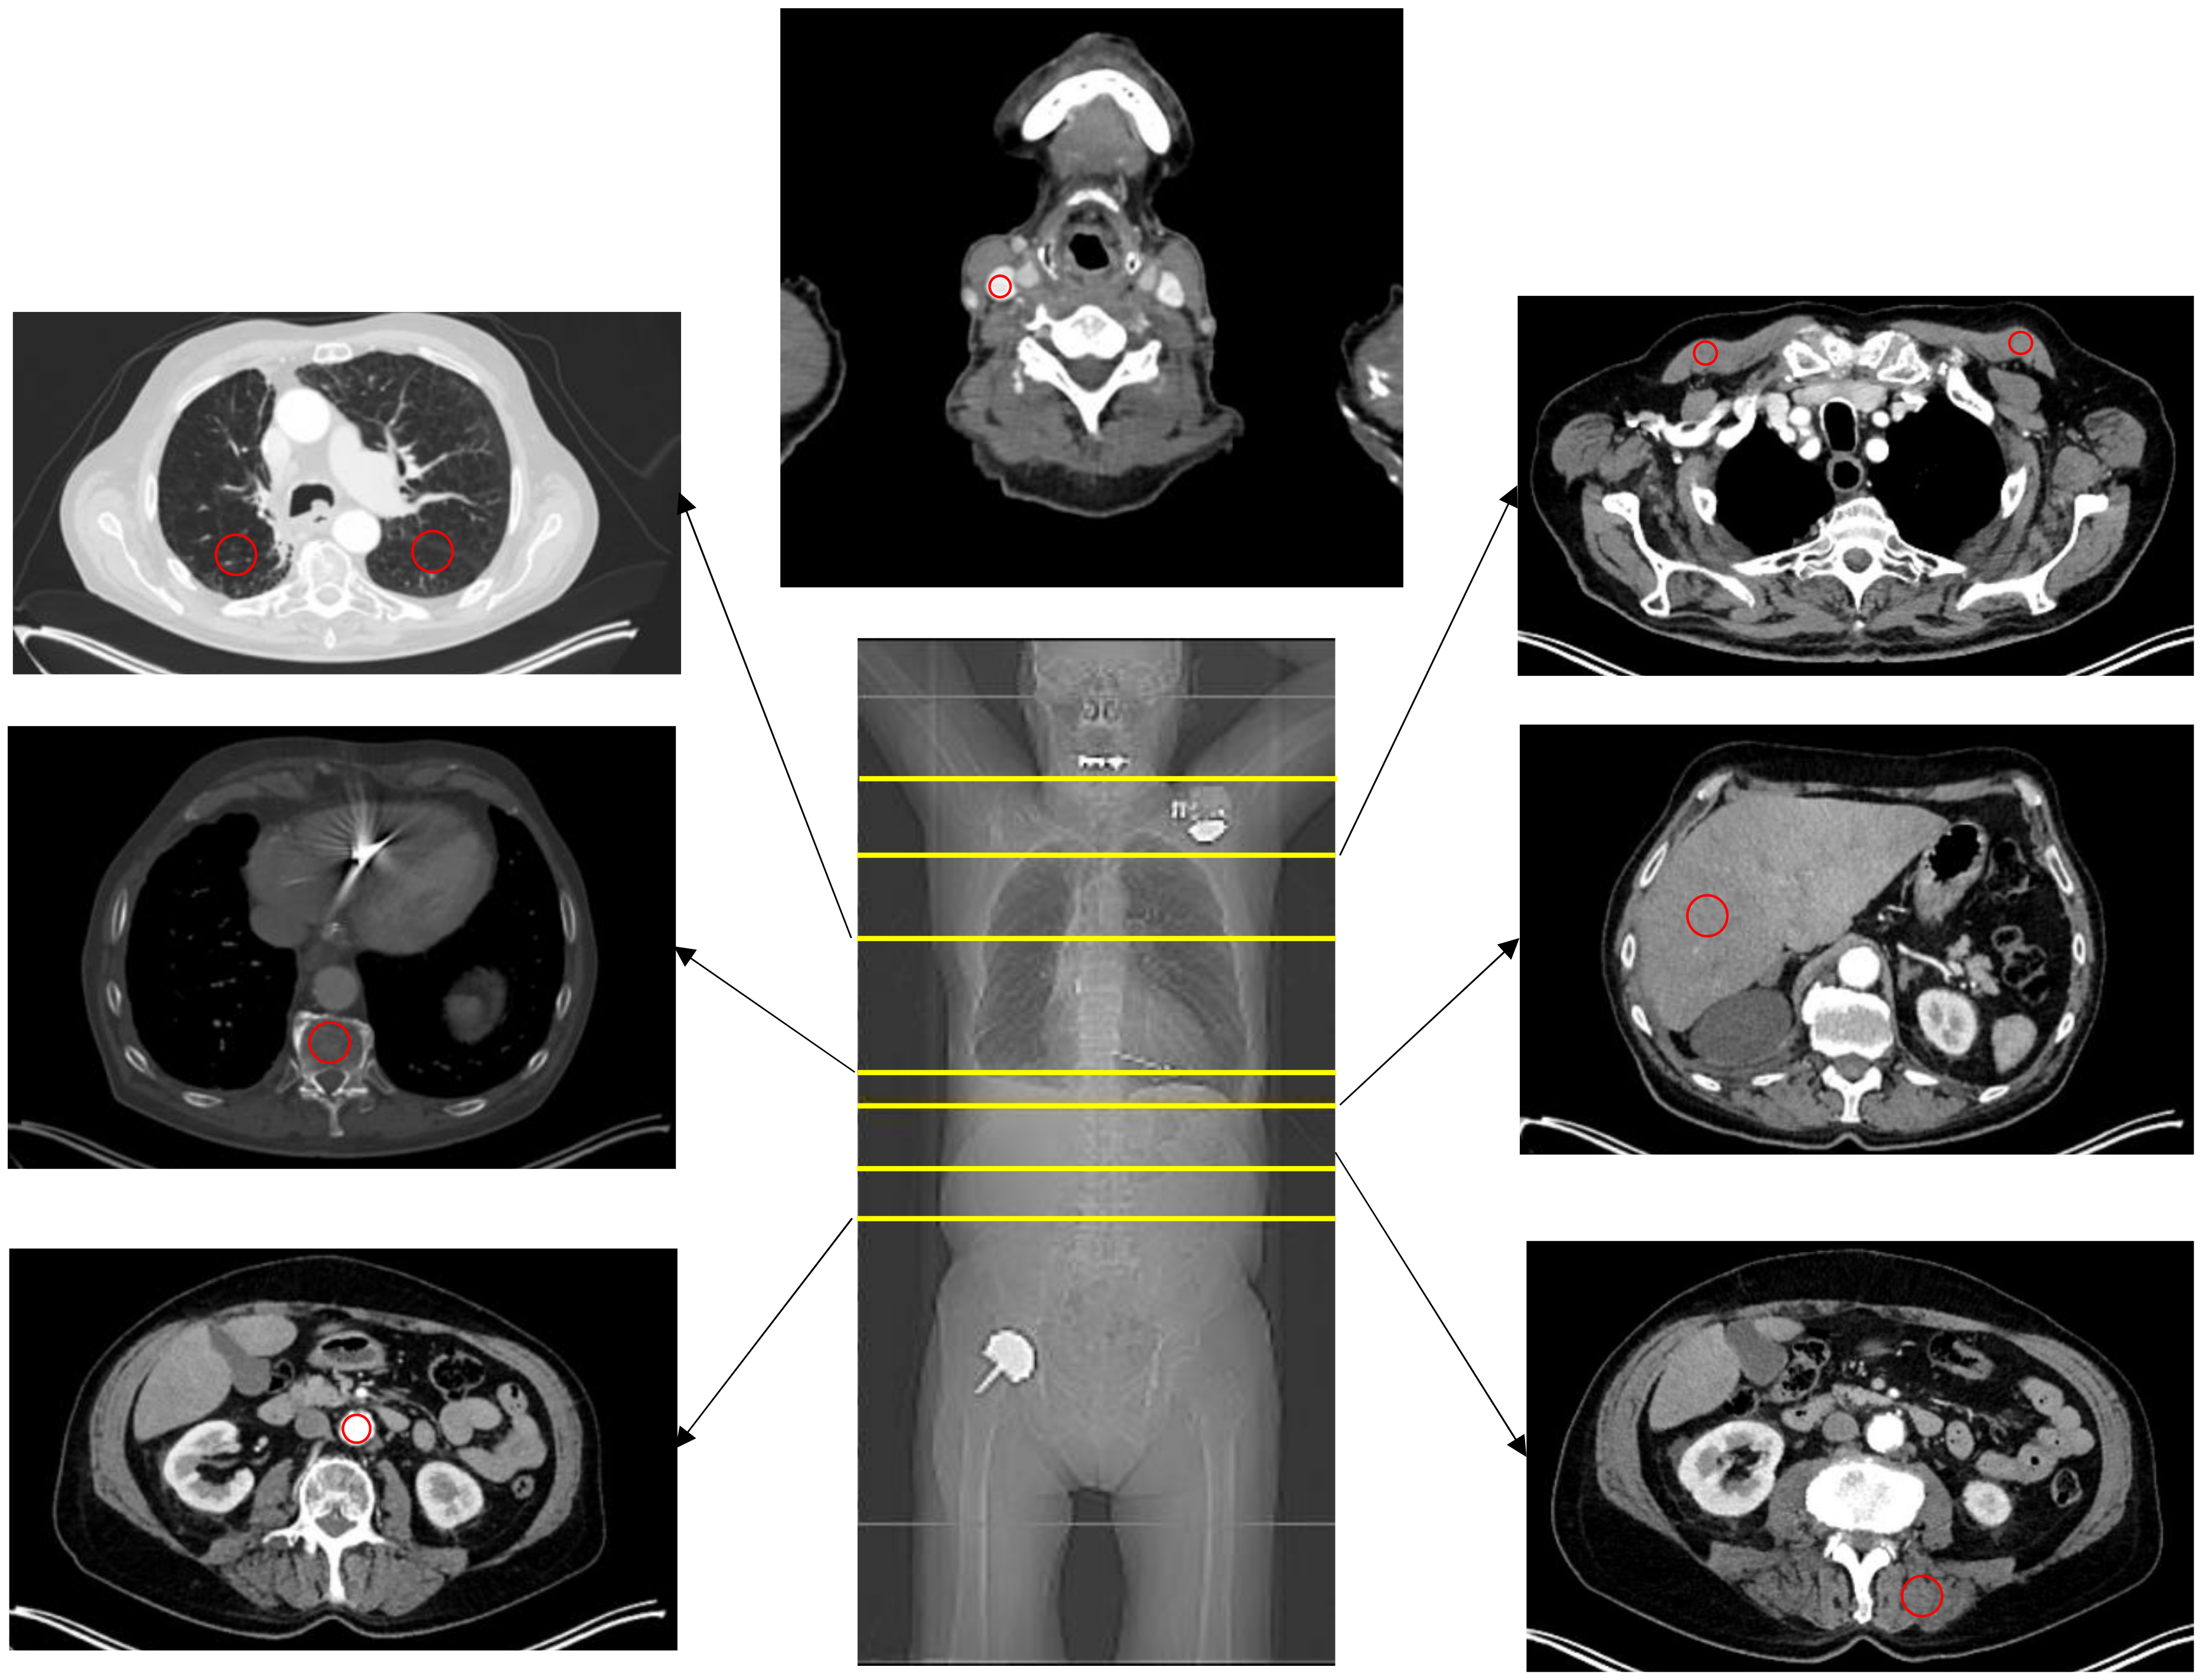

2.5. Image Analysis